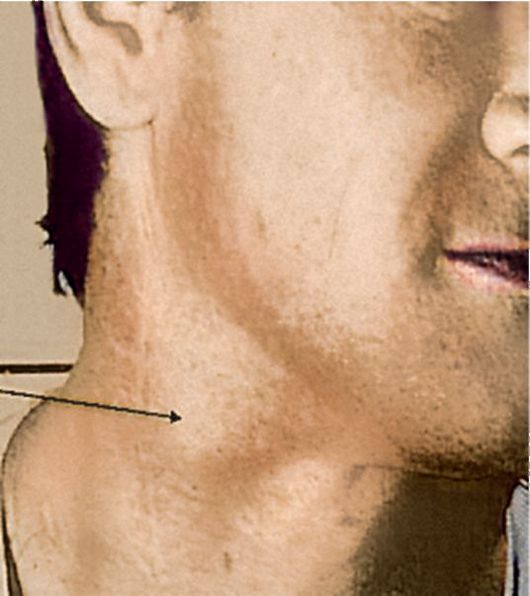

УЗИ лимфоузлов при лимфоме Ходжкина